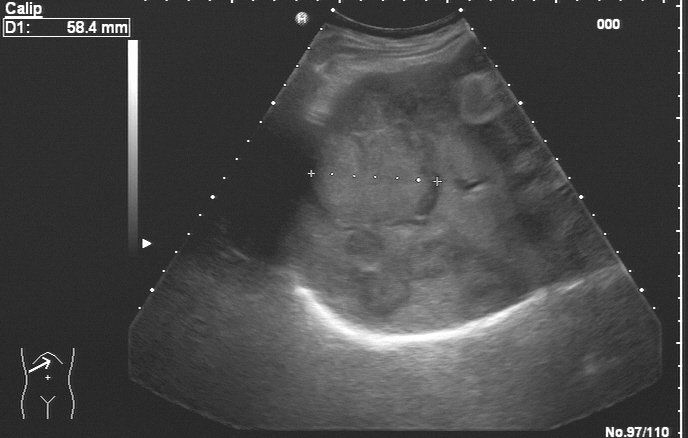

Hepatologie

Für Patienten mit Lebererkrankungen bieten wir eine Spezialsprechstunde an. Neben einer ausführlichen Diagnostik (incl. Leberbiopsie, wenn notwendig) wird eine Therapie und Überwachung von Patienten mit folgenden Erkrankungen angeboten:

• Langzeitbetreuung von Patienten mit Leberzirrhose jeder Genese (HCC-Vorsorge)